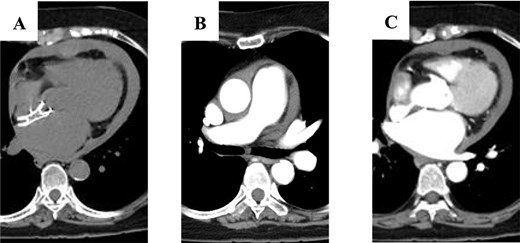

An 81-year-old woman developed sudden chest pain after bathing and was admitted to our hospital. She had undergone percutaneous closure of ASD with FFII at another hospital 5 years previously. The patient was also receiving immunosuppressive drugs for rheumatoid arthritis. She was in shock on arrival. Computed tomography showed circumferential pericardial effusion without aortic dissection and extravascular leakage of the contrast medium (Fig. 1A–C). Emergency pericardial drainage was performed, and 450 mL of blood was drained. Although the cardiac tamponade was relieved, and the patient’s condition improved temporarily, blood drainage from the pericardial sac persisted. She was immediately transferred to the operating room for emergency surgery. We found that part of the device was exposed out of the right atrium, and a pinhole perforation with an ulcer was observed on the aortic wall adjacent to the exposed device; this was diagnosed as FFII-induced erosion (Fig. 2A). The aorta was obliquely incised to confirm that there was only a perforation without an intimal ulcer (Fig. 2B), the perforation was repaired with felt sandwich sutures, and the aorta was closed in two layers. The right atrium was then incised, and the device was easily removed by pulling the center pole and folding the device (Fig. 2C). The ASD and right atrial injury were closed with a bovine pericardial patch. The patient had a favorable postoperative course and was discharged without any major complications.

Computed tomography scan showing: (A) circumferential pericardial effusion; (B) no aortic dissection; and (C) no extravascular leakage of contrast media.